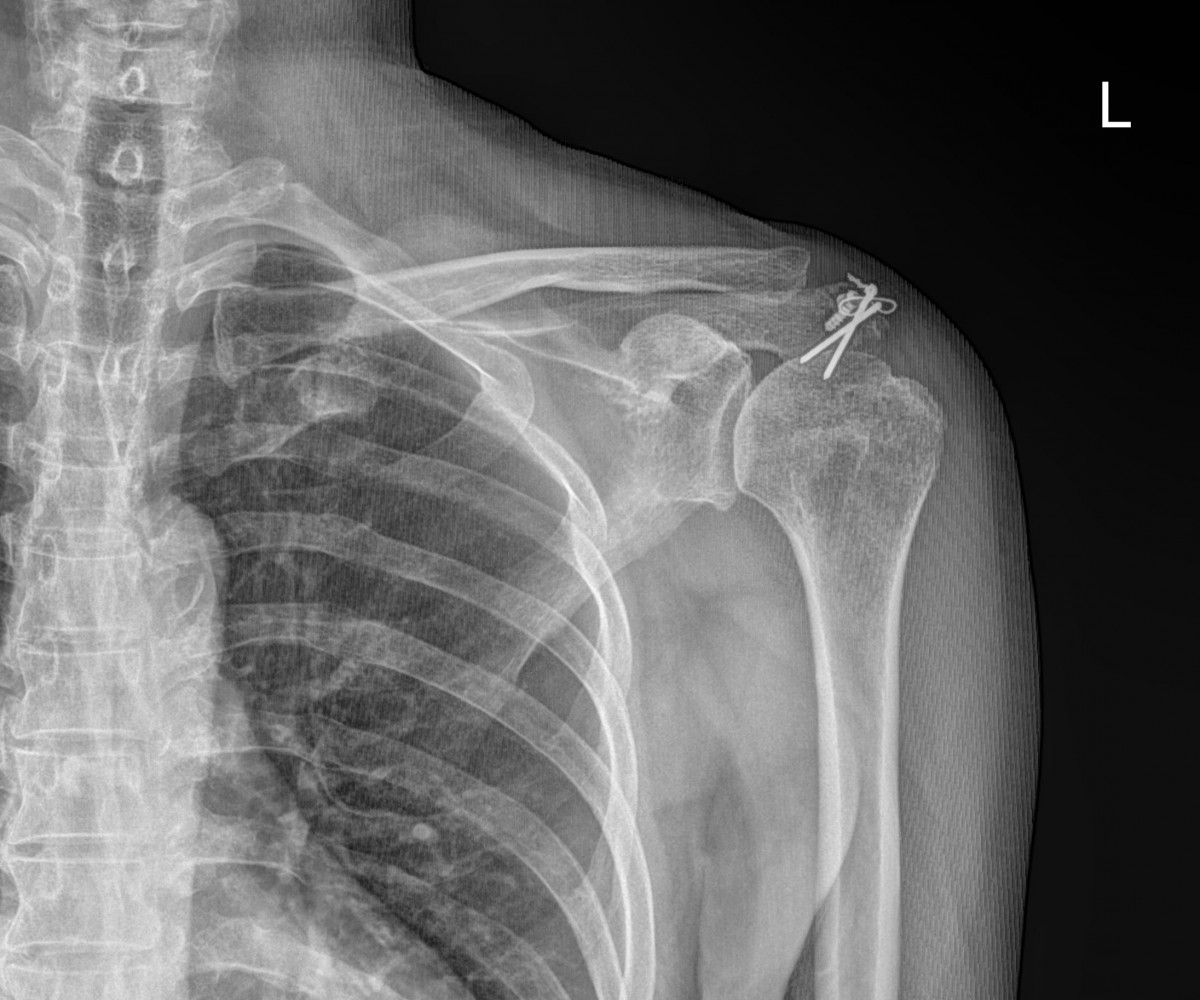

배우한원장님 어깨 관절낭염 수술 및 내고정 금속 제거술 (1954)최동O 환자

작성자 최고관리자 댓글 0건 조회 1,920회 작성일 22-02-23 15:45